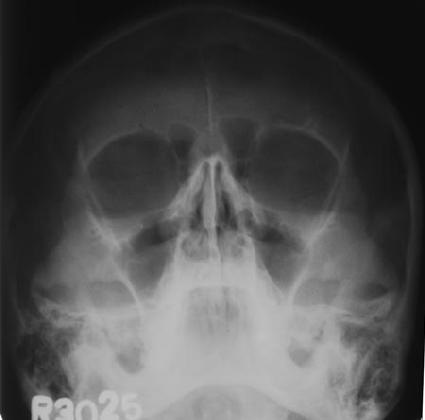

Since last few days, this headache had been worst and finally, I decided to see a doctor. He advised me for a PMS X-Ray.

PMSXray

Well, on first look, I was happy to see that it did not show any nail or a knife in my skull or brain... It also did not show any tumor as it did not show if a brain is there or not... Since PMS x-ray can not show eyeballs, I assumed that eyeballs are not the cause....

When Dr saw this x-ray, he goes: "Oh, so you got frontal sinusitis!." Too bad too bad... He prescribed me Cefpodoxime 200mg (2D) to cure the infection, Lemoson 500mg (2D) as decongestant and Levocetrizine 5mg(1D) for anti-allergy. Its third day of this treatment and I had no headaches for last two mornings. So, yes, the medicine is working!